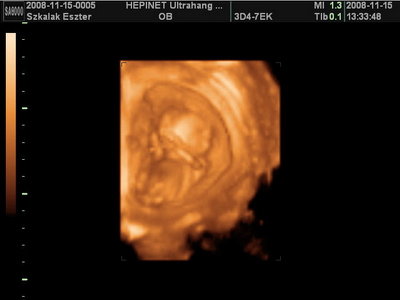

A legújabb hírem, hogy szombaton voltam UH-n és hát egyre nagyobb kisbabám, és most már biztosan kislányom van!!!! Már 10 cm-es az ülőmagassága ás hát kb. 120 gr. A doki szerint minden rendben vele, megméregetett mindent, aztán megnéztük a szívecskéjét, a veséjét, gyomrát, szemecskéjét, szóval legeltettük a szemünket a kicsi drágán. Most sokkal nyugodtabb volt és bár kissé szégyenlősen néha elfordult, meg védekezőn a kezét maga elé vette, azért megmutatta, amit szerettünk volna látni rajta.